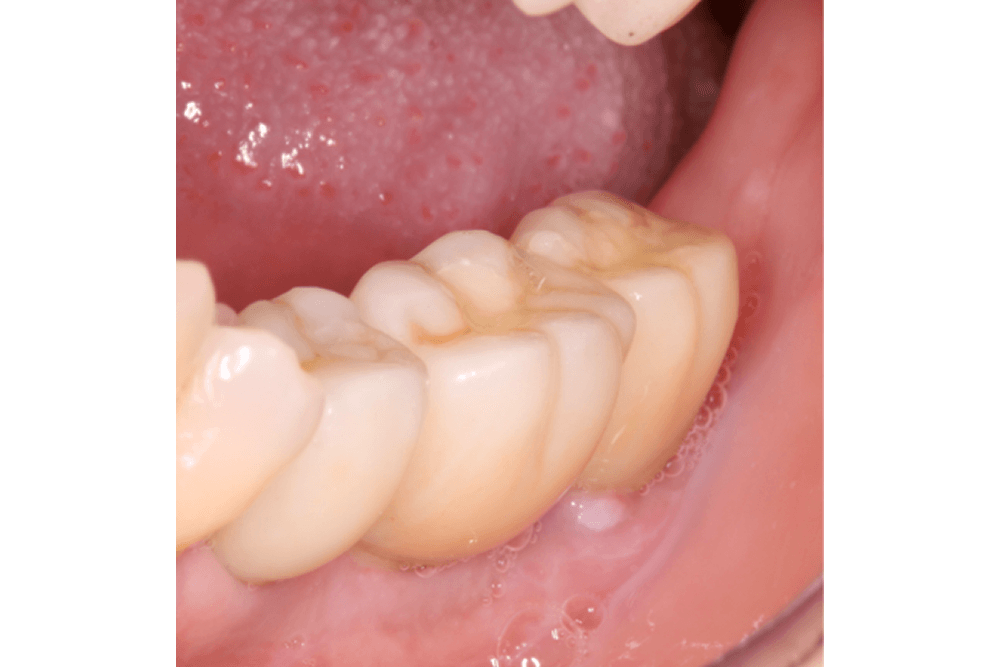

Próteses Fixa sobre dente

Tem a função de substituir um ou mais dentes perdidos ou destruídos. São próteses fixas na boca, presas sobre dentes e feitas de porcelana, podendo ser unitária ou múltipla (quando une três ou mais dentes para suprir uma ou mais ausência dentária).

Pode-se considerar também como prótese fixa, os laminados cerâmicos conhecidos como facetas e lentes de contato dental, mais indicados para o paciente que busca melhorar a estética em dentes anteriores.